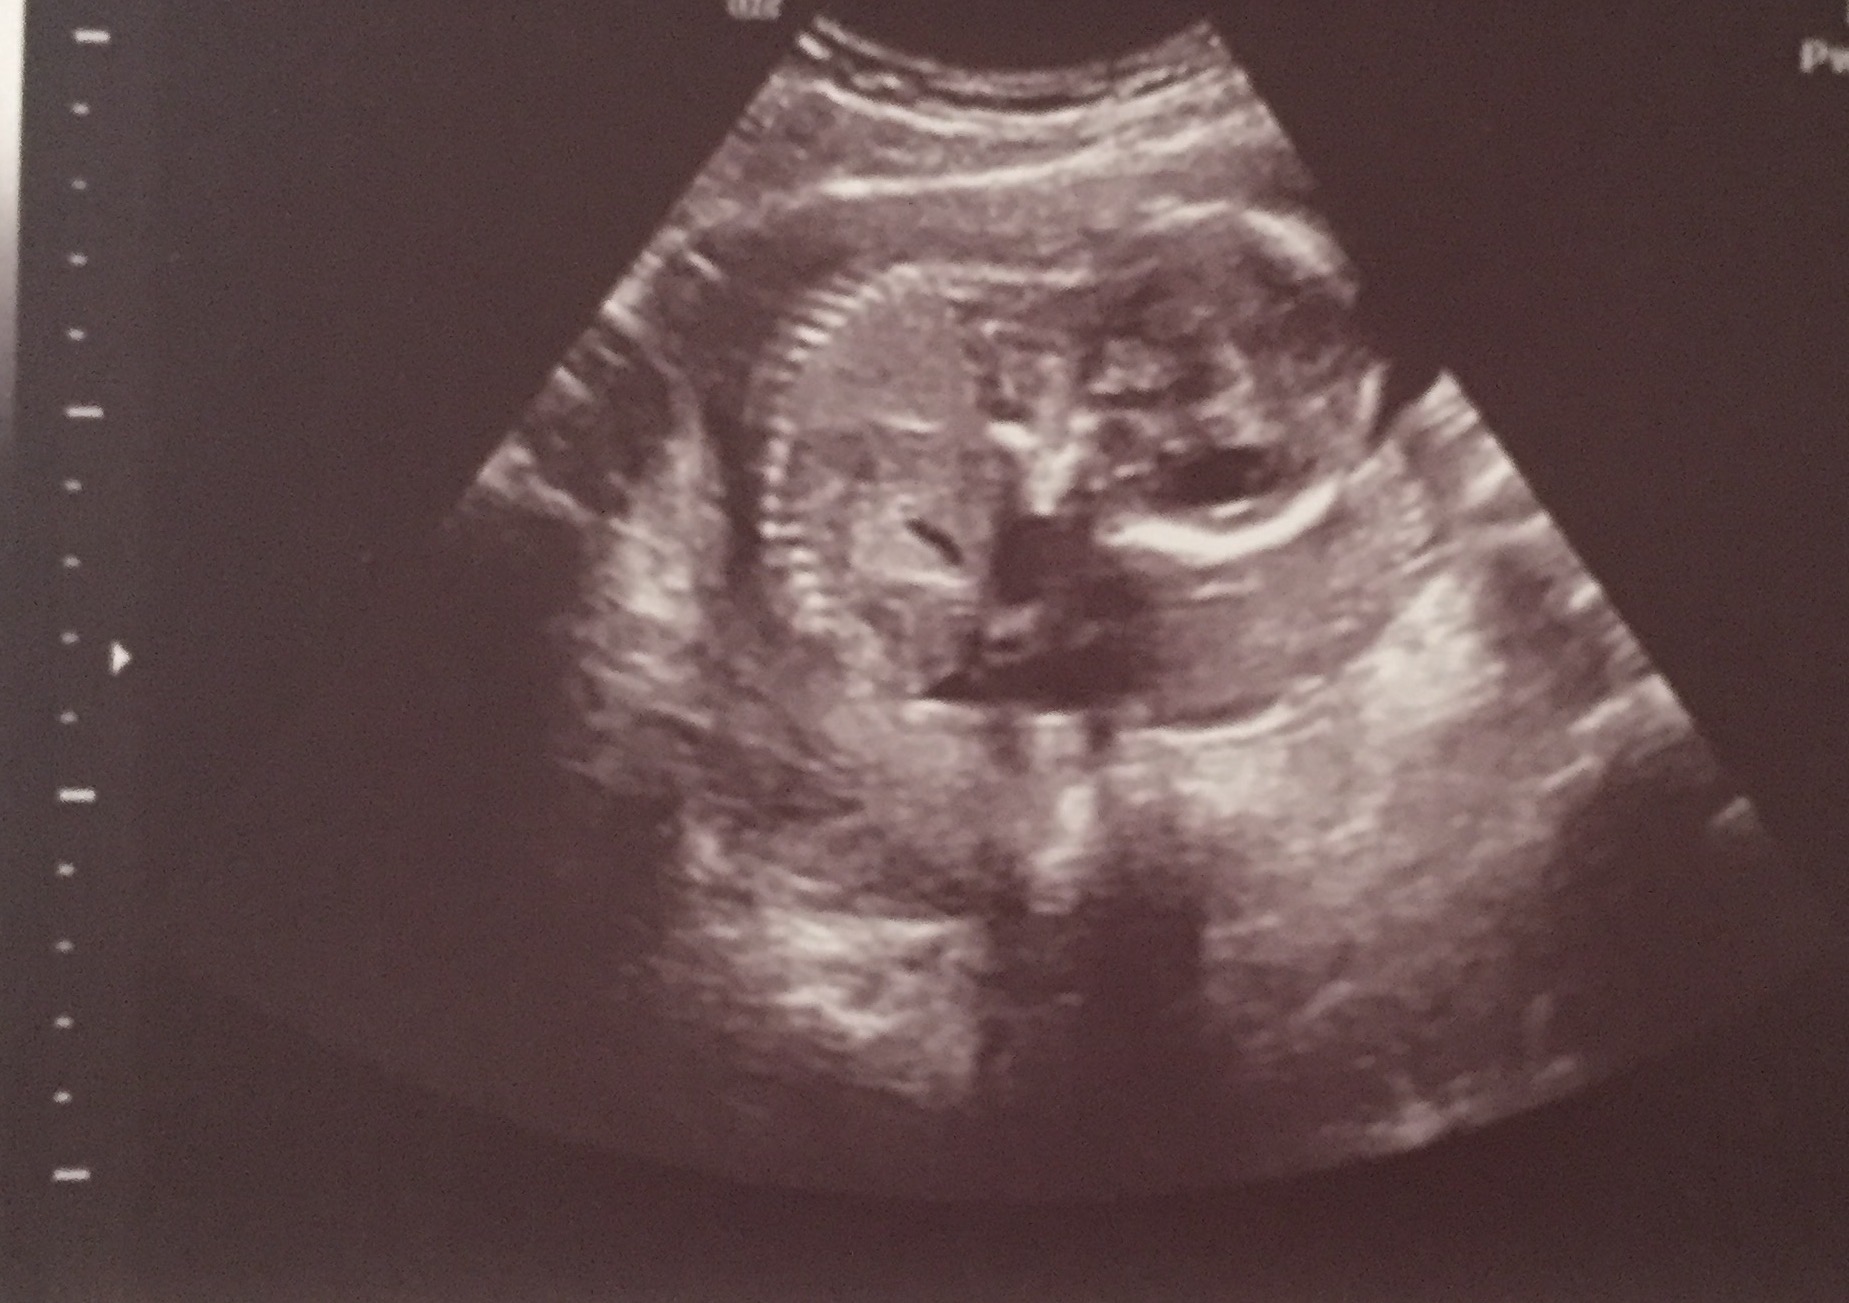

I had an elected 2d/4d ultrasound at 16 weeks and 3 days. The baby wasn't all that cooperative and the umbilical cord was between it's legs, blocking it's genitals. The baby lifted it's leg for a second and the ultrasound technician said that she saw the "hamburger buns" (labia). She continued trying to get the baby to open it's legs to get a clear shot and she said that she saw the three white lines of the vaginal bones multiple times and that she was confident it was a girl. She took a 2d picture of the supposed lines (picture below). However, she could not get a clear 3d shot because the baby would not open its legs to get a clear shot. I am curious to get others opinions on my ultrasound and if it looks like a girl or if it looks like it could be a boy because I don't want to tell everyone it's a girl and then be surprised at my 19 week scan when they tell me it's a boy.Attachment 35763Attachment 35764Attachment 35765Attachment 35766Attachment 35767